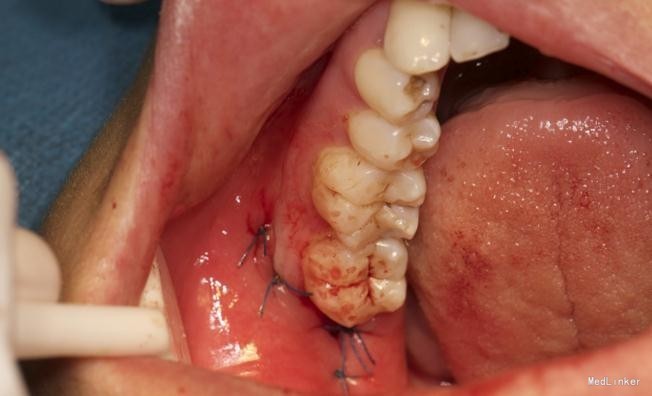

左下8水平阻生拔除

患者,男,25岁,要求拔除左下颌水平阻生牙齿,平素体质一般,无药物、食物过敏史,无高血压、心脏病等系统病史

拔除术